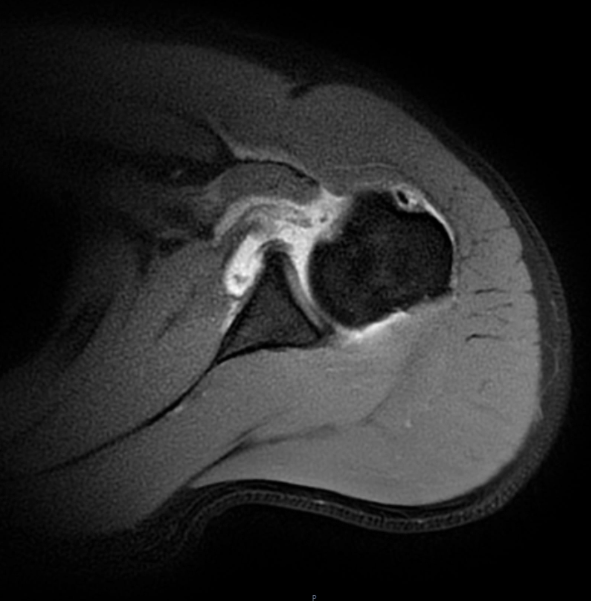

张华主任经过细致查体,怀疑这是肩胛下肌损伤。进一步的磁共振检查印证了判断,李先生肩胛下肌的止点位置撕裂了。“掰手腕时瞬间的力量不平衡,就像猛拉一根绷紧的绳子,很容易导致肩胛下肌急性撕裂。”张主任解释,李先生的这种损伤若不及时修补,肌肉会慢慢萎缩,不仅影响肩关节力量,还可能导致长期功能障碍。